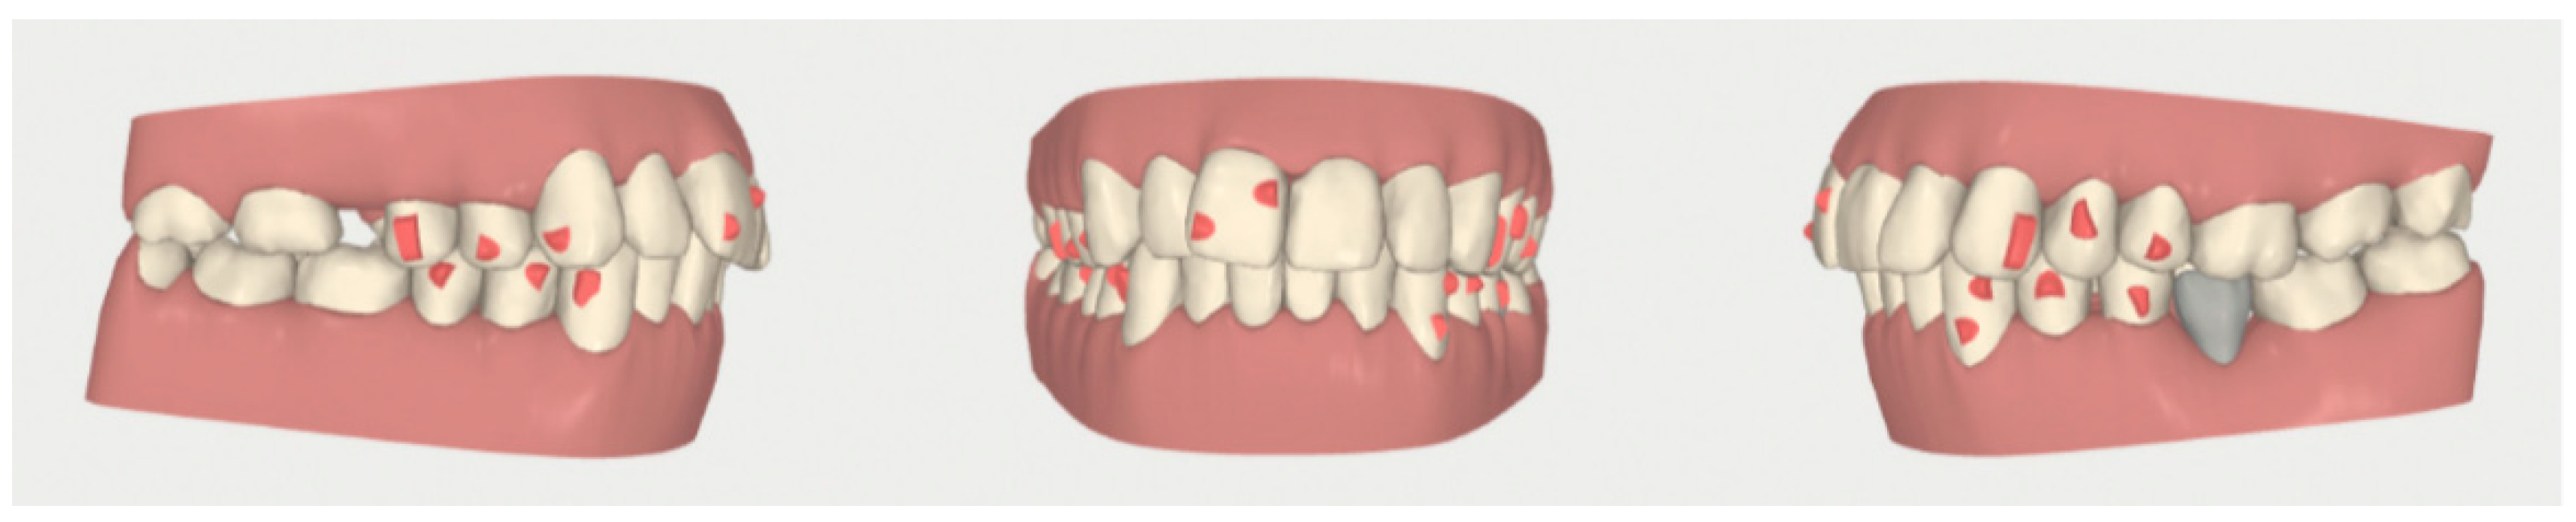

2.2. Orthodontic Planning

2.3.1. Example—Anterior Open-bite

2.3.2. Example 2—Extraction Space Closure